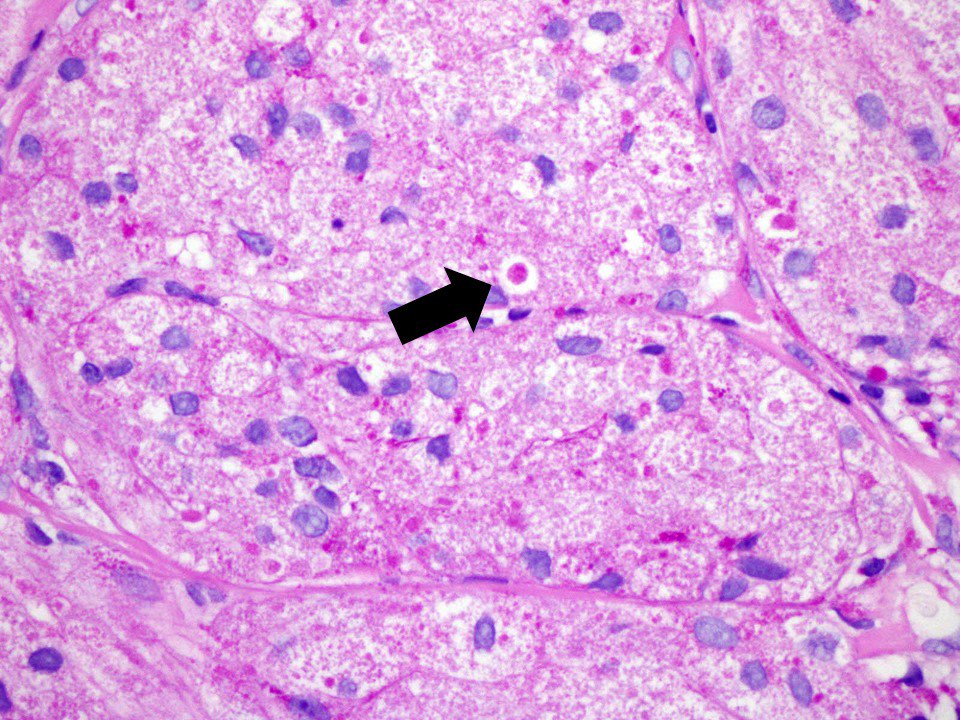

Pustulo-ovoid bodies of Milian granular cell tumor #pathology #SurgPath #bstpath Marypoppins Laura G. Pastrián MD Dr Phil Bryant ncbi.nlm.nih.gov/pubmed/17448196